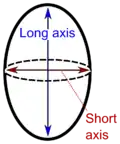

- Size, where lymphadenopathy in adults is often defined as a short axis of one or more lymph nodes is greater than 10mm.[28]

- By size, where lymphadenopathy in adults is often defined as a short axis of one or more lymph nodes is greater than 10mm.[28][29] However, there is regional variation as detailed in this table:

Lymphadenopathy of the axillary lymph nodes can be defined as solid nodes measuring more than 15 mm without fatty hilum.[35] Axillary lymph nodes may be normal up to 30 mm if consisting largely of fat.[35]

In children, a short axis of 8 mm can be used.[36] However, inguinal lymph nodes of up to 15 mm and cervical lymph nodes of up to 20 mm are generally normal in children up to age 8–12.[37]

Lymphadenopathy of more than 1.5–2 cm increases the risk of cancer or granulomatous disease as the cause rather than only inflammation or infection. Still, an increasing size and persistence over time are more indicative of cancer.[38]